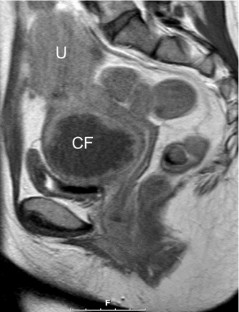

Selective Embolisation of a Heavily Bleeding Cervical Fibroid in a Pregnant Woman

We report a case of a 20-week pregnant woman, who underwent embolisation of a cervical fibroid to end a life-threatening massive bleeding. This is the first reported case in the literature of a super-selective uterine fibroid embolisation (UFE) in a pregnant woman, even though pregnancy is considered an absolute contraindication for UFE. This rare case demonstrates that UFE can be safely performed during pregnancy providing an excellent short- and long-term clinical outcome for both mother and child.

Fig. 1

Fig. 2

Fig. 3